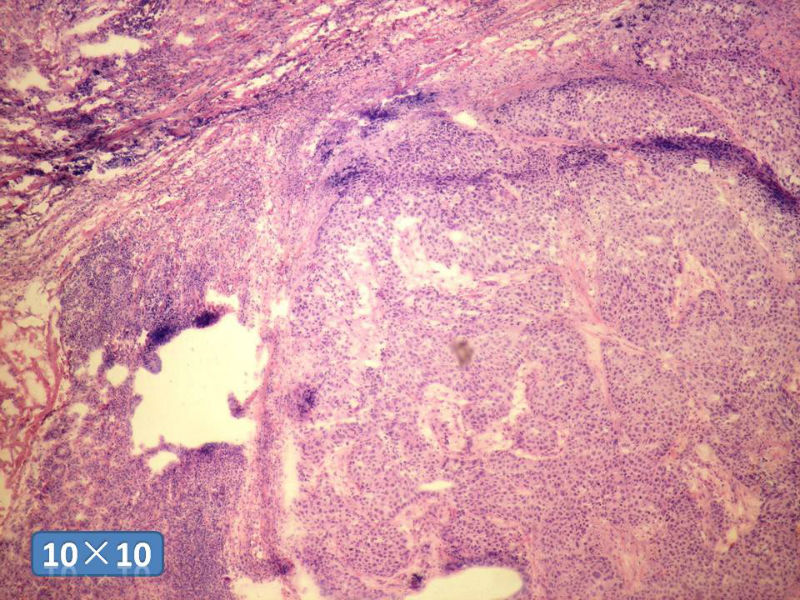

女性,50岁,乳腺肿物,冰冻切片(图1-25)

HE